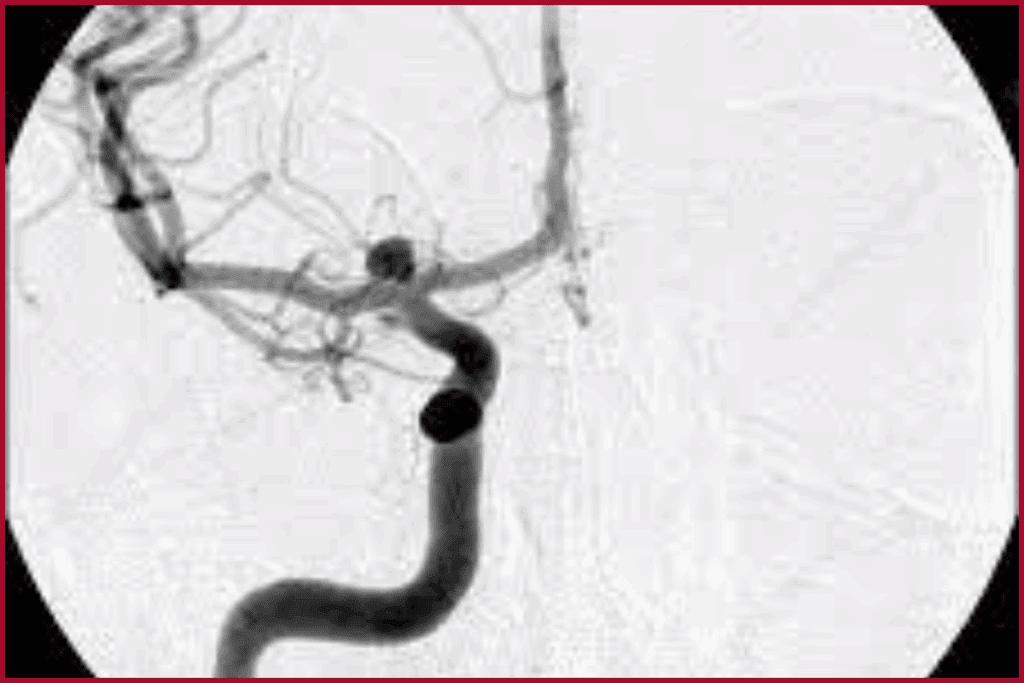

CT Angiography (CTA) of the Neck

CT Angiography (CTA) is a special CT scan for blood vessels. It uses contrast material to make arteries stand out, helping spot blockages.

Contrast-Enhanced Imaging

Contrast-enhanced imaging makes blood vessels more visible during CTA. A contrast agent is injected into the blood. This helps show the arteries clearly against other tissues.

3D Reconstruction Capabilities

CTA can make 3D models of the carotid arteries. This lets doctors see blockages or stenosis in more detail.

Conventional Angiography